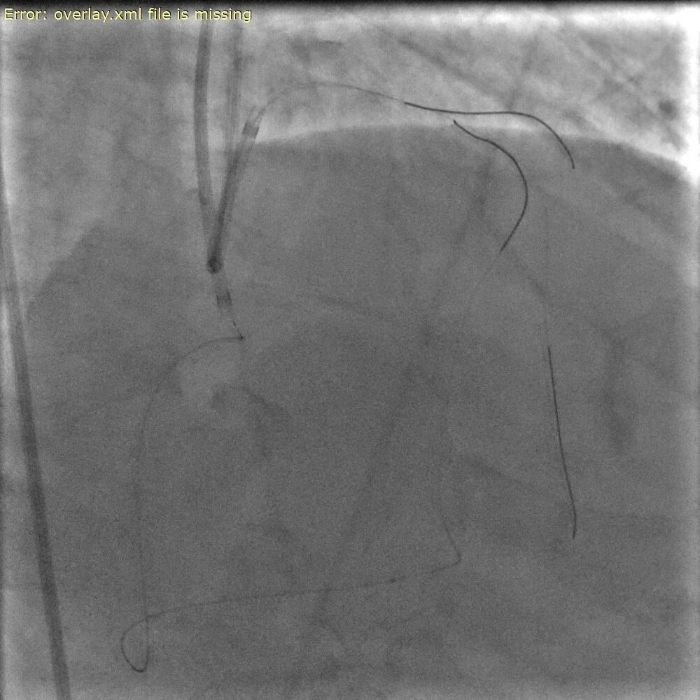

患者为62岁男性,此次入院前反复胸痛,伴有一次心源性晕厥的发生,就诊我院完善冠脉造影示前降支血管近段完全闭塞,为CTO病变,其余两支冠脉血管均有重度狭窄,因病变复杂且风险极高,建议家属首选外科搭桥手术,但经过反复沟通后患者及家属希望尝试微创介入治疗。

手术中,郭旭主任与团队成员密切协作,经过3个小时的不懈努力,在正向导丝技术通过失败的情况下,灵活更换多种治疗策略,最终通过更具挑战性的逆向CTO-PCI技术经侧支循环精准通过闭塞段,成功开通左前降支闭塞病变,全程操作流畅,术后患者无并发症,症状显著缓解。

△术前、术中、术后